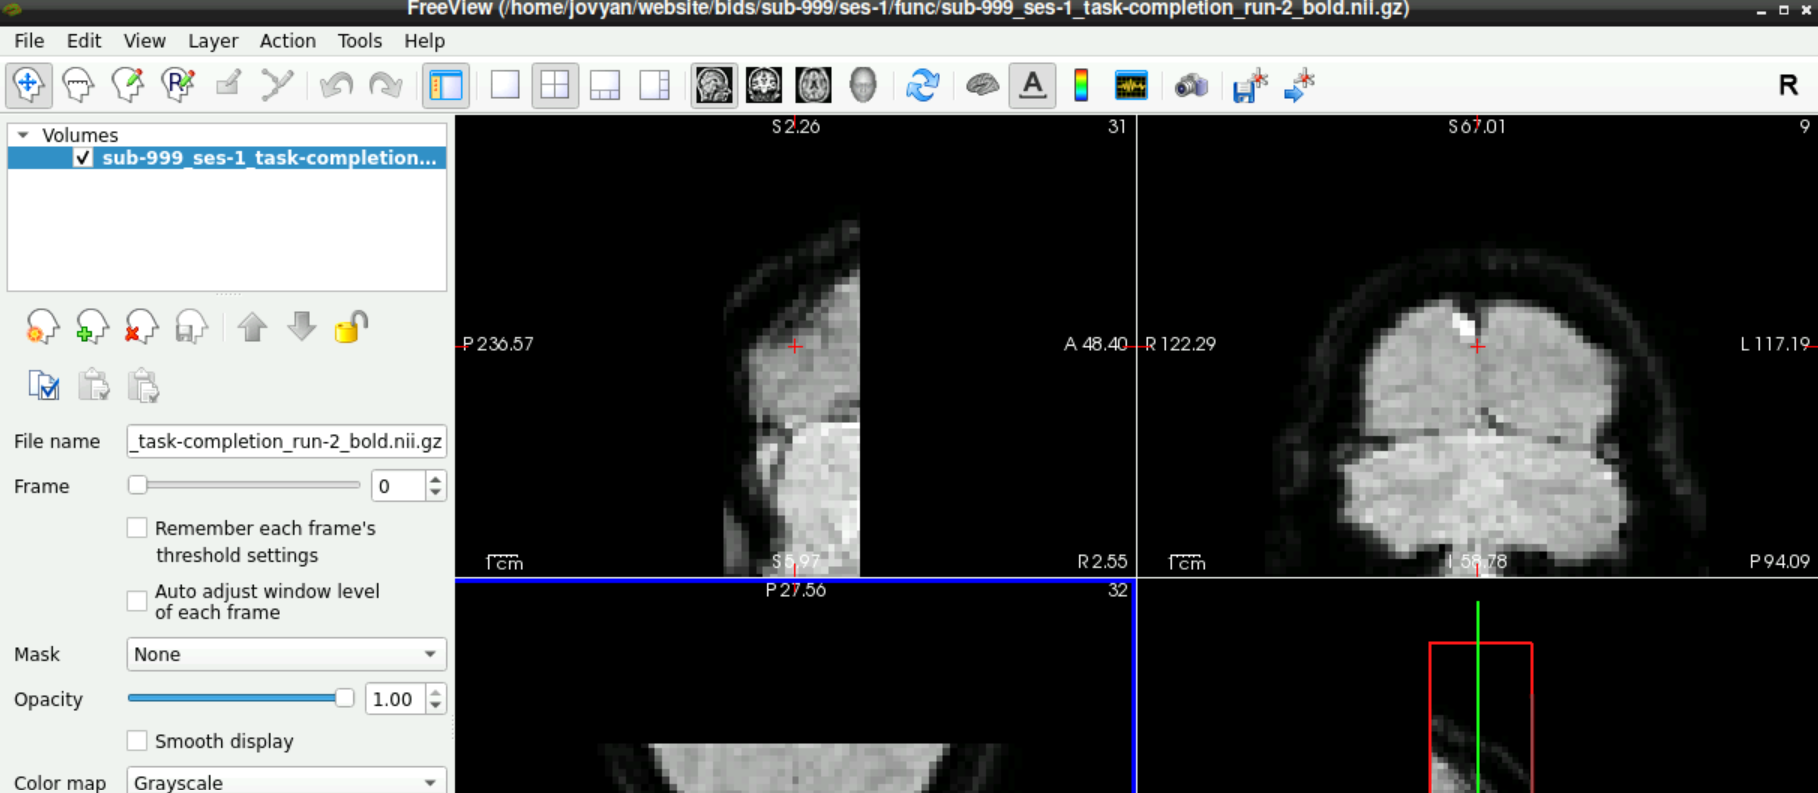

When the volume loaded, it should see some kind of data and something that looks like a brain:

1.3 Check for Denoising Scan

To check if a denoising scan is included in you data, use the slider next to Frames (left side, roughly in the middle), to navigate to the last frame. If a denoising sequence was used during data acquisition in the scanner, this frame looks “empty”. Toggle between the last and second to last frame, to visualize the difference even more